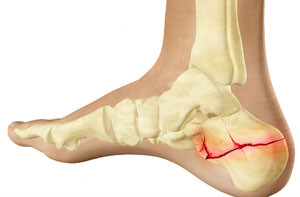

Из всех возможных типов перелома, такое нарушение целостности костной ткани – явление нераспространенное (всего 4% среди переломов других костей скелета). Чаще бывает вследствие падения с большой высоты. Сама же пяточная кость одна из самых прочных в строении стопы. Чтобы ее повредить, потребуется достаточно большое усилие. Как следствие – минимальное количество случаев с легкой формой перелома. Обычно же травма достаточно тяжелая, лечение сложное и продолжительное.

Статистические данные свидетельствуют, что более 80% случаев такого травмирования возникает по причине сильного удара пяткой о твердую поверхность в результате падения человека с большой высоты. Гораздо реже кости ломаются из-за чрезмерного сдавливания или прямого попадания тупого предмета в область пяточной кости (удара).

Односторонние разрывы происходят чаще, чем множественный перелом пяточной кости. Нередко травма сопровождается нарушением целостности костных тканей лодыжки, плюсневых костей, а также позвоночника (что очень редко).

Перелом пятки является серьезной травмой, которая требует внимательного подхода к диагностике и лечению. Врачи отмечают, что основные признаки включают сильную боль в области пятки, отек и затрудненное движение. Важно сразу обратиться за медицинской помощью, так как неправильное лечение может привести к долгосрочным последствиям, таким как хромота или хроническая боль.

Имея часть клинической картины (характерную симптоматику), врач проводит осмотр и направляет на рентгенографию стоп обеих конечностей. Рентген делается в двух проекциях: боковой и аксиальной. Снимок требуется для того, чтобы:

Поэтому и нужен рентген обеих стоп (больной и здоровой). Первое, на что обращает внимание специалист при чтении снимка, – каков суставно-бугорный угол (угол Белера). Нормальное значение этого угла – 20-40 градусов. При травме пятки значение угла изменяется – уменьшается или даже уходит в минус. Исходя из этого критерия, пациента будут лечить соответственно.